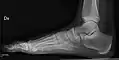

- Ankle - AP/Mortice and Lateral

Ankle - frontal

15 degrees internal rotation

Lateral (this one a bit suboptimal by not seeing straight through the ankle joint)

Lateral oblique (to visualize the posterior border of the tibia)